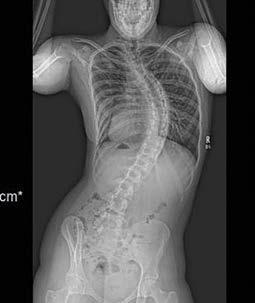

Are

At Nicklaus Children’s Orthopedic, Sports Medicine and Spine Institute, we ignite hope for children like Mikaela, diagnosed with severe scoliosis. Our specialized care and successful operation corrected her scoliosis granting her the freedom to live an active life. It’s no surprise that Nicklaus Children’s is recognized as Florida’s leader for pediatric orthopedic care by the U.S.News & World Report in its 2023-24 Best Children’s Hospital’s rankings. Our team leads with compassion and delivers extraordinary care, emphasizing why this is the place where your child matters most.